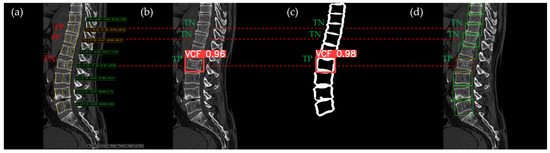

Figure 10, Figure 11, Figure 12, Figure 13 and Figure 14 illustrate typical examples of results for HLR, EEVD, TSVD_SD, and TSVD_DC in patients with acute VCFs. The results of applying different methodologies to the same patient image and identical slice locations were as follows. In the HLR results, each vertebra was marked with yellow solid lines indicating the height measurement lines for the anterior, middle, and posterior regions. The measured height values and HLR percentages were displayed on the right side of the image. If the HLR percentage ranged between 25% and 40%, it was highlighted in orange, while values of 40% or higher were highlighted in red. In the EEVD results, the VCF detection outputs were displayed along with their respective confidence scores based on the input patient images. For the TSVD_SD results, after performing spine segmentation, the model extracted only the spine contour, and the VCF detection results with their corresponding confidence scores were presented. In the TSVD_DC results, bounding boxes were generated for each vertebral body, with normal vertebrae represented in green and vertebrae identified as VCFs displayed in red.

In Figure 13, the L1 vertebra was normal, whereas a VCF was present at the L2 level. This patient exhibited irregular cortical endplate appearances from T11 to L2. Radiological evaluation concluded that there was an acute VCF only at the L2 level, which the HLR method failed to detect. However, all convolutional neural network (CNN)-based methods—EEVD, TSVD_SD, and TSVD_DC—successfully detected the VCF at L2 by extracting and analyzing specific features of spinal images. In TSVD_DC, there was an additional FP, as the model incorrectly identified a VCF at L1.

Figure 13. The VCF detection results from four different methods. (a) HLR, (b) EEVD, (c) TSVD_SD, and (d) TSVD_DC. The acute VCF, as confirmed by the radiologist, was located at the L2 level. TP, TN, FP, and FN were marked at the same level with a red dotted line. The HLR was low at L2, which was the reason for the FN in (a). The L1 vertebra was misclassified as VCF by TSVD_DC.